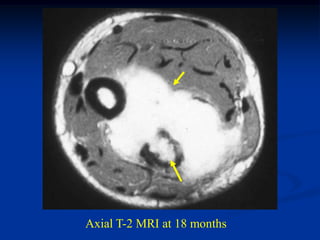

Axial T-2 MRI at 18 months

Axial T-2 MRIat 18 months